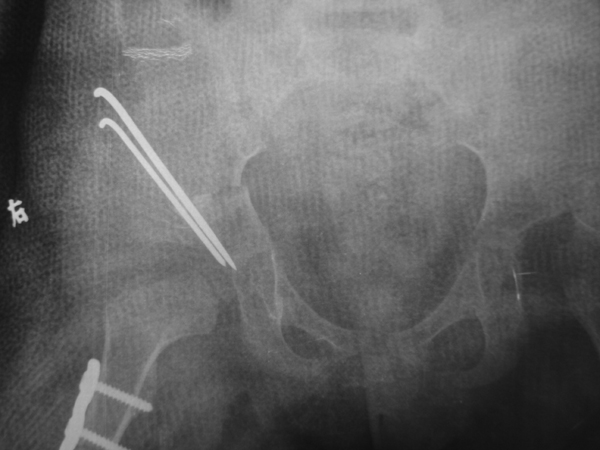

先天性髋关节脱位:各种年龄组先天性髋脱位的治疗是我科的传统强项,根据年龄和不同的病理状态,采取不同的个性化的治疗方案,其治愈率在省内处于领先水平。

图4.双侧先天性髋关节脱位右侧骨盆切开复位、骨盆截骨、股骨截骨治疗术后关节复位好